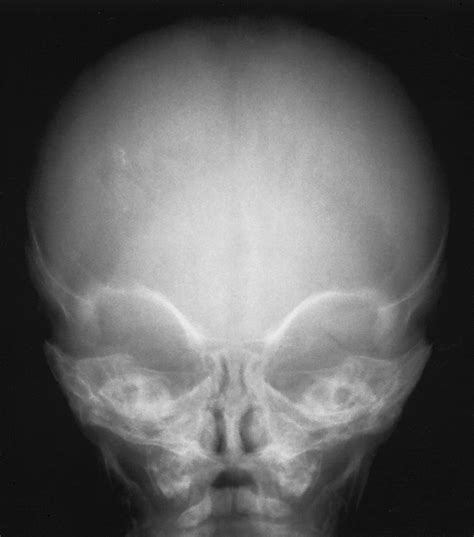

A Baby Skull Xray is a radiographic imaging technique used to visualize the bones of a baby's skull. This non-invasive procedure is essential for diagnosing various conditions, including fractures, deformities, and developmental abnormalities. The X-ray images provide a detailed view of the skull's structure, helping healthcare providers make informed decisions about treatment and care.

Interpreting Baby Skull Xray results requires a trained eye and a deep understanding of pediatric anatomy. Here are some key points to consider:

• Bone Density: The density of the bones can indicate the presence of fractures or other abnormalities.

• Skull Shape: The shape of the skull can provide insights into developmental issues or deformities.

• Fontanelles: The soft spots on a baby’s skull, known as fontanelles, should be checked for proper closure and any signs of swelling or bulging.

• Sutures: The sutures, or the fibrous joints between the skull bones, should be examined for any signs of premature fusion or separation.

Several common findings can be identified through a Baby Skull Xray. Understanding these findings is essential for accurate diagnosis and treatment:

• Fractures: Visible cracks or breaks in the skull bones.

• Deformities: Abnormal shapes or structures of the skull.

• Infections: Signs of infection, such as bone erosion or swelling.

• Tumors: Abnormal growths or masses within the skull.

• Developmental Abnormalities: Issues with the development of the skull, such as premature fusion of sutures.